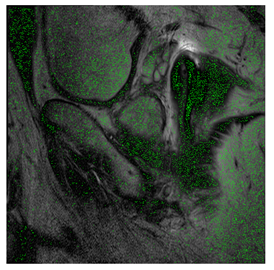

4.3. The Results

In this subsection, we describe three experiments used to measure the performance of the proposed method. The first experiment shows the stegoimage and marks the pixels’ positions that have been modified during the embedding process, as shown in Table 2, Table 3, Table 4, Table 5, Table 6 and Table 7. To make modified pixel positions have a pronounced effect, we set bpp (bit per pixel) rate at 0.05 and 0.025. It can be seen from the results that the proposed local complexity function can distinguish ROI and RONI from most of the medical images, so modified pixels are mainly gathered in RONI. However, it is observed that the proposed local complexity function cannot distinguish between ROI and RONI in the Prostate-MRI database due to the relative complexity of the image. Besides, “Modified BPP” represents the proportion of pixels in the image that have been modified. We observed that the performance of “baboon” in the grayscale standard images database is poor because that image’s pixels are relatively complex. It becomes challenging to select the more embeddable pixels based on the proposed local complexity function. Nevertheless, the modified pixel positions in other grayscale standard images, such as Lena and Barbara, are relatively smooth, verifying that our local complexity function is also applicable to general images.